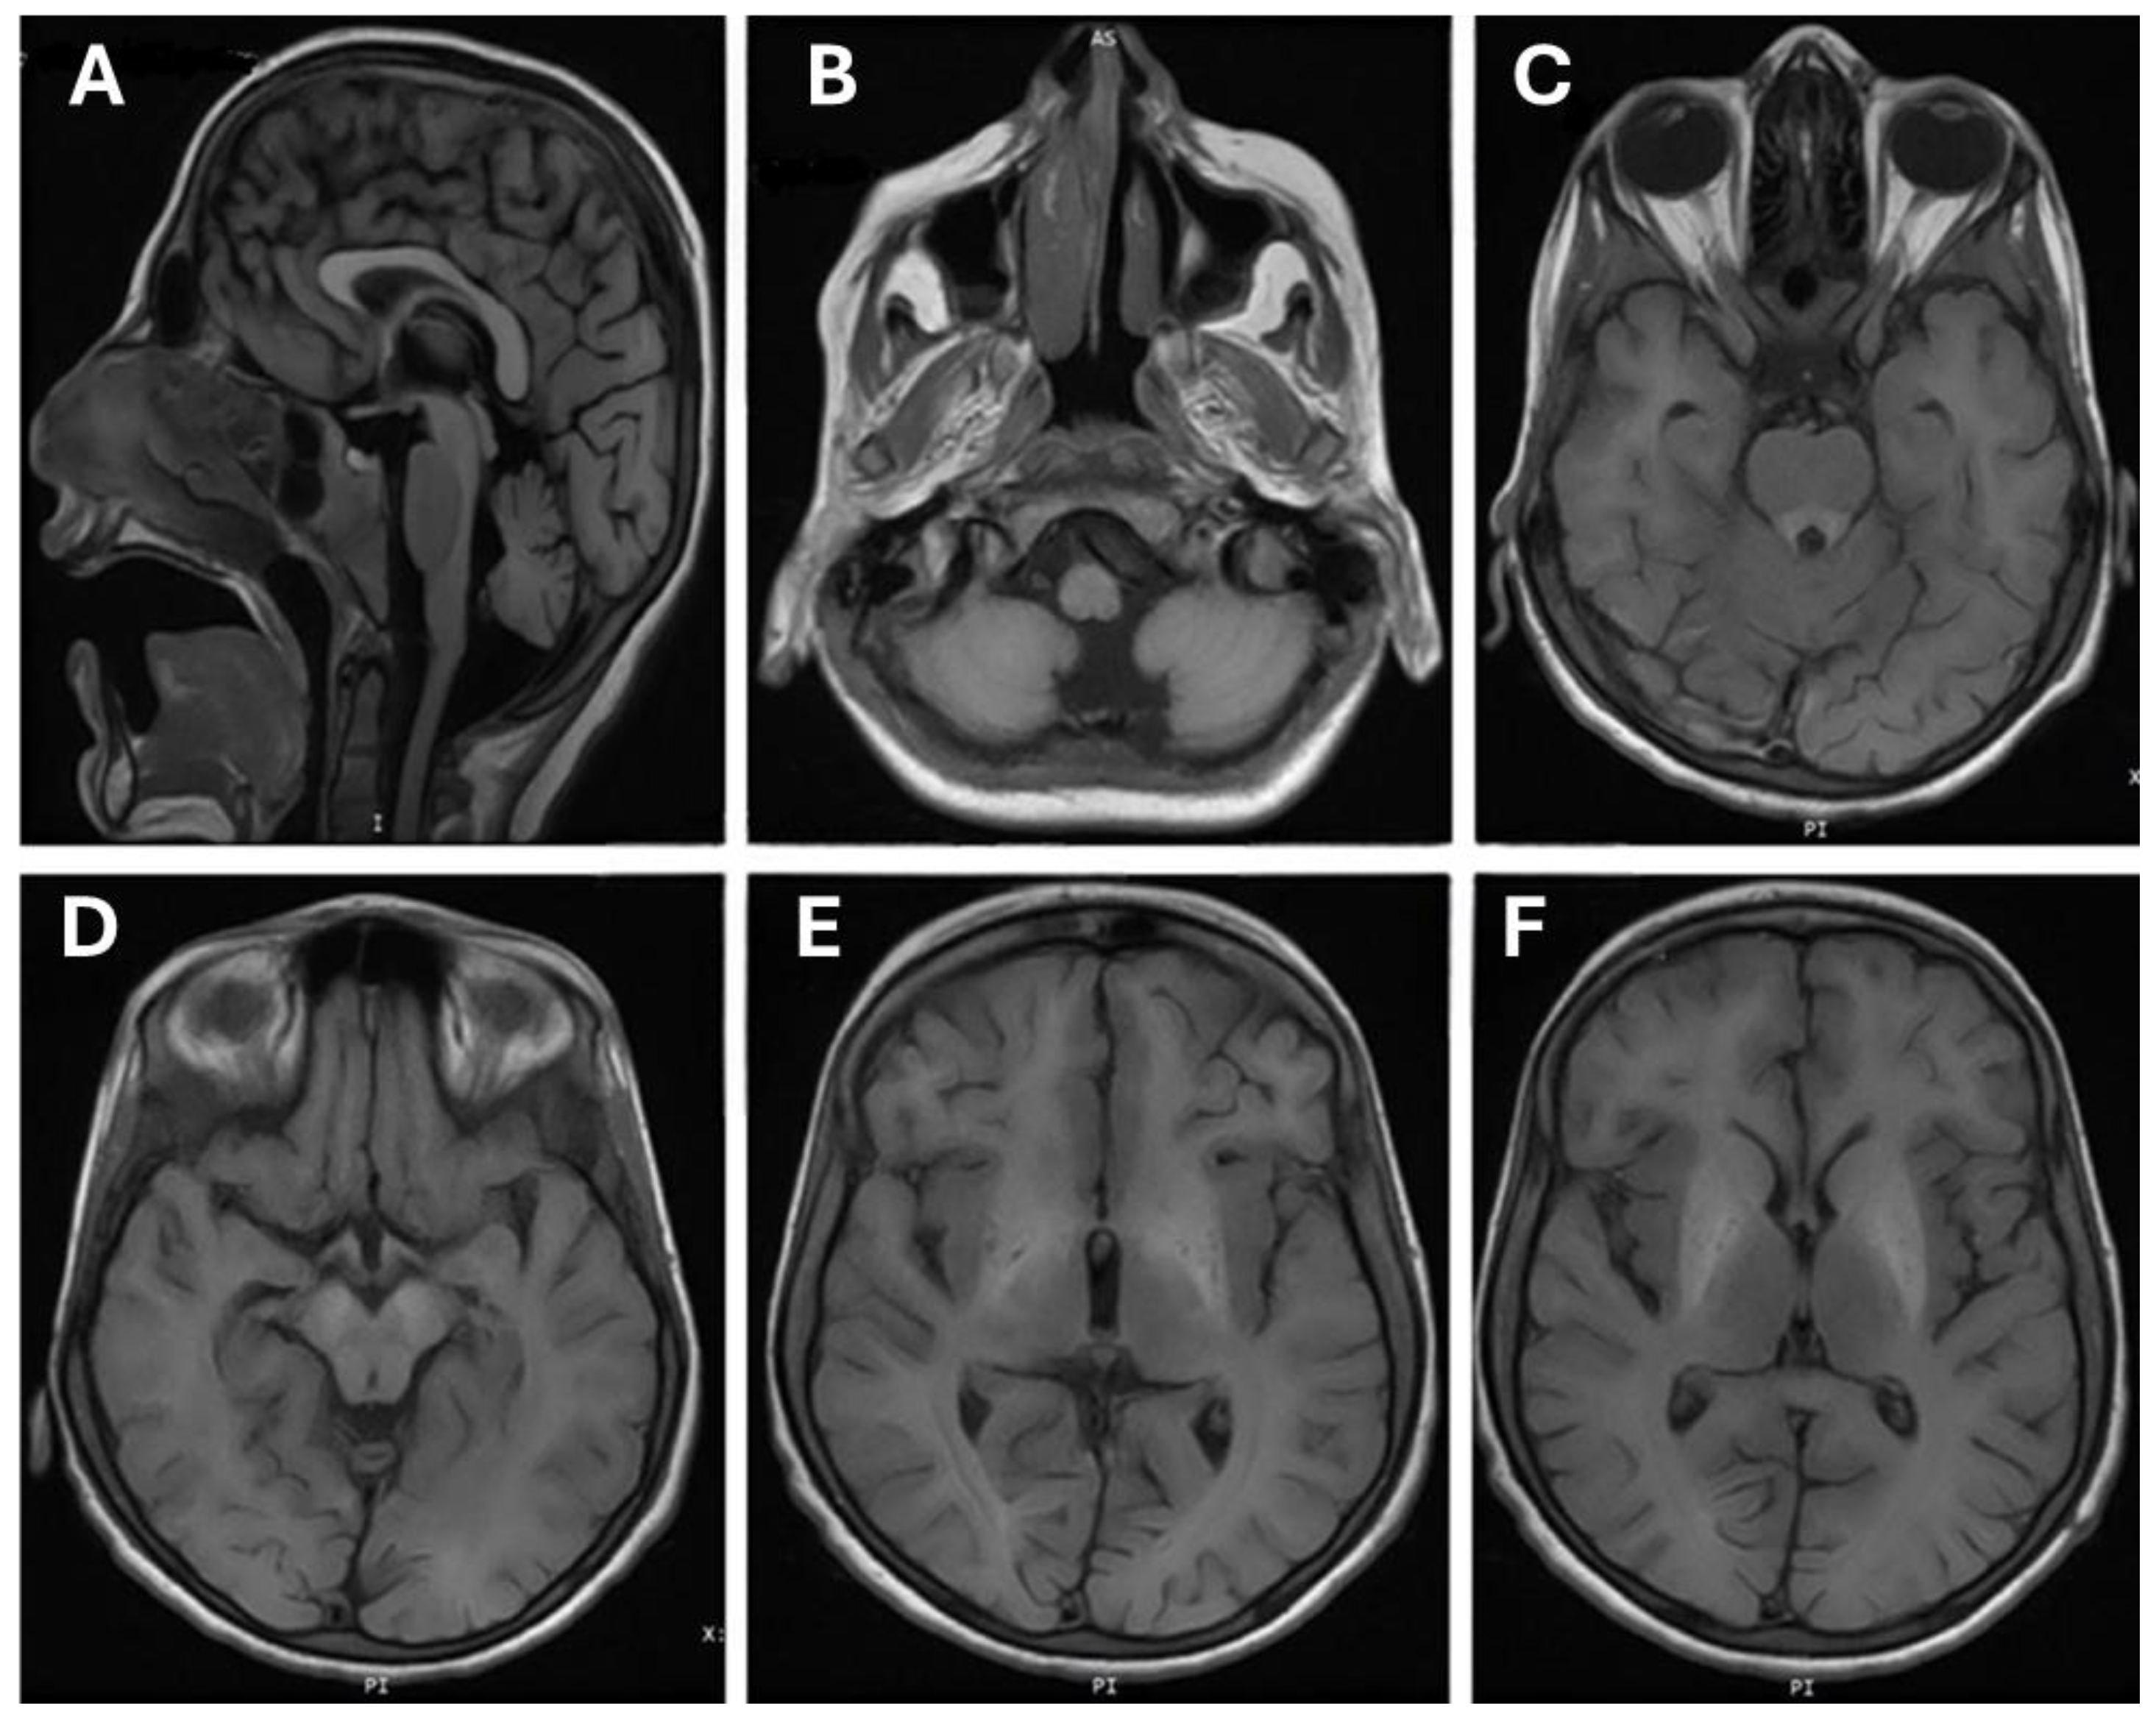

3.2. Brain MRI Finding

| Brain MRI Findings | ||

| Hyperintensities in the basal ganglia | Yes | N/A |

| White matter lesions | Yes | N/A |

| Anterior pituitary lesions | No | N/A |